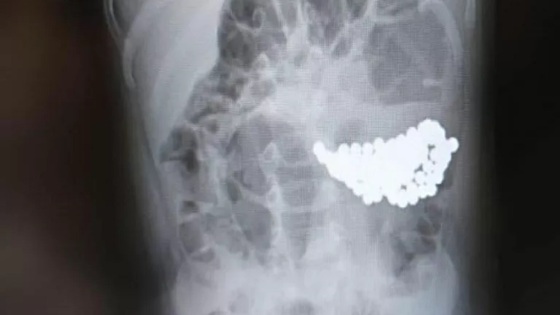

По словам завотделения больница в Екатеринбурге Кирилла Кожина, самыми опасными для детей являются конструкторы из магнита в форме разноцветных шариков, электронные и музыкальные игрушки, содержащие дисковые батарейки, гидрогелевые игрушки, а также конструкторы из неметаллических материалов.

Так, ранее сообщалось о двухлетнем ребенке, проглотившем 100 разноцветных магнитных шариков. Другой малыш играл с металлическим медальоном и случайно проглотил его.